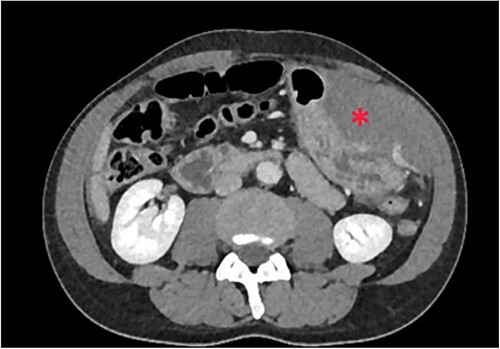

Non-contrast abdominal computed tomography (CT) revealed hemoperitoneum: moderate ascites with organized clot on the surface of greater omentum (Fig. 1)

Computed tomography image on admission: moderate ascites with organized clot.